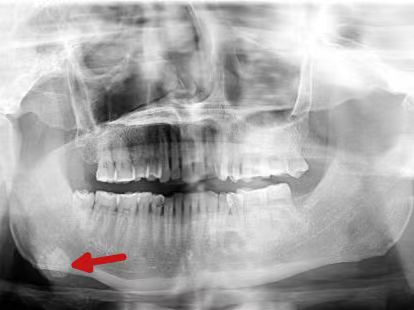

然而,近一个月来,肿痛日益加剧,且口底出现黄白色脓性渗出物,他这才急忙前往医院就诊。接诊医生龙静为谭先生完善检查后发现,他的口底竟藏着一颗约1.2厘米的“石头”,最终确诊为颌下腺导管结石。入院后,谭先生接受了全麻下“颌下腺切除术+颌下腺导管结石取出术”,目前术后恢复良好,已顺利出院。